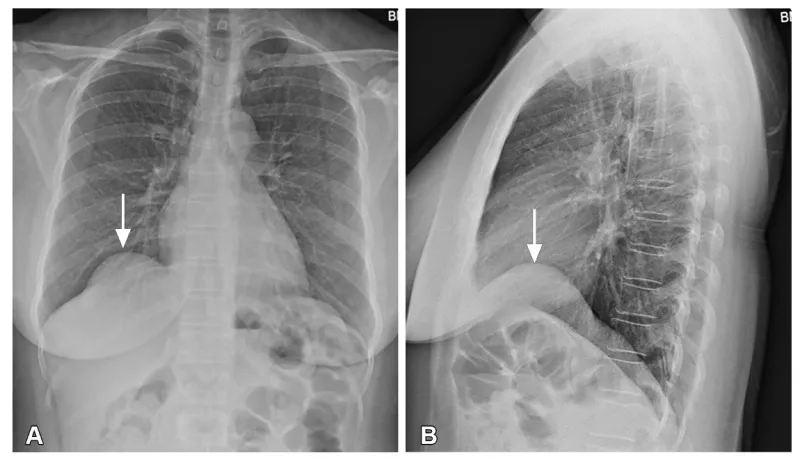

Gambar Eventrasio Diafragma X-Ray | Sumber: NCBI

Eventrasio diafragma adalah kondisi ketika posisi diafragma naik secara tidak normal akibat otot yang lemah atau lumpuh.

Akibatnya, diafragma pun kehilangan kemampuan berkontraksi dengan baik sehingga paru-paru tertekan dan fungsi pernapasan terganggu.